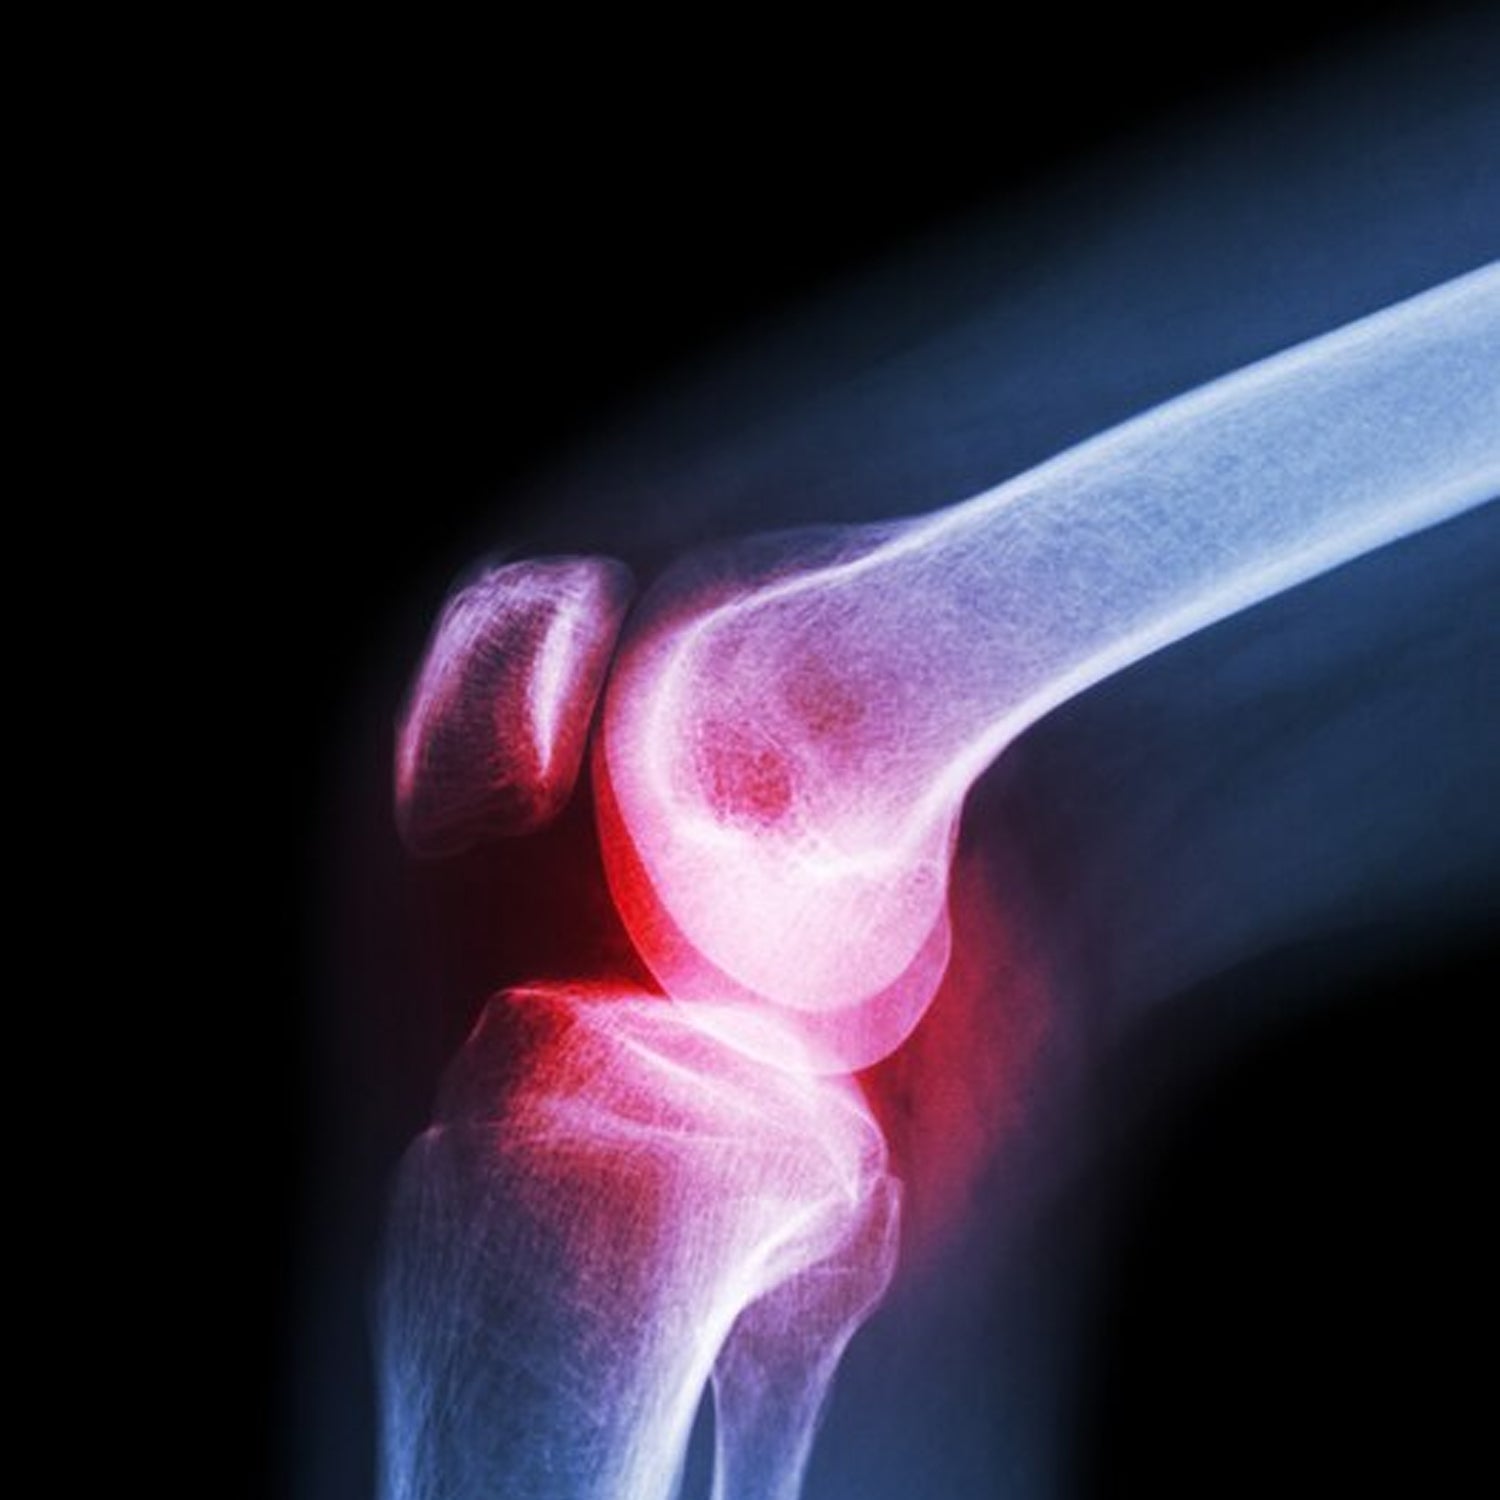

(XL) Knee Cap for Knee Support

Knee Cap for Knee Support (XL) Description :- The Knee Cap provides sufficient support to the knee joint. It is...

₹268.00 inc. tax View ProductQuick View -